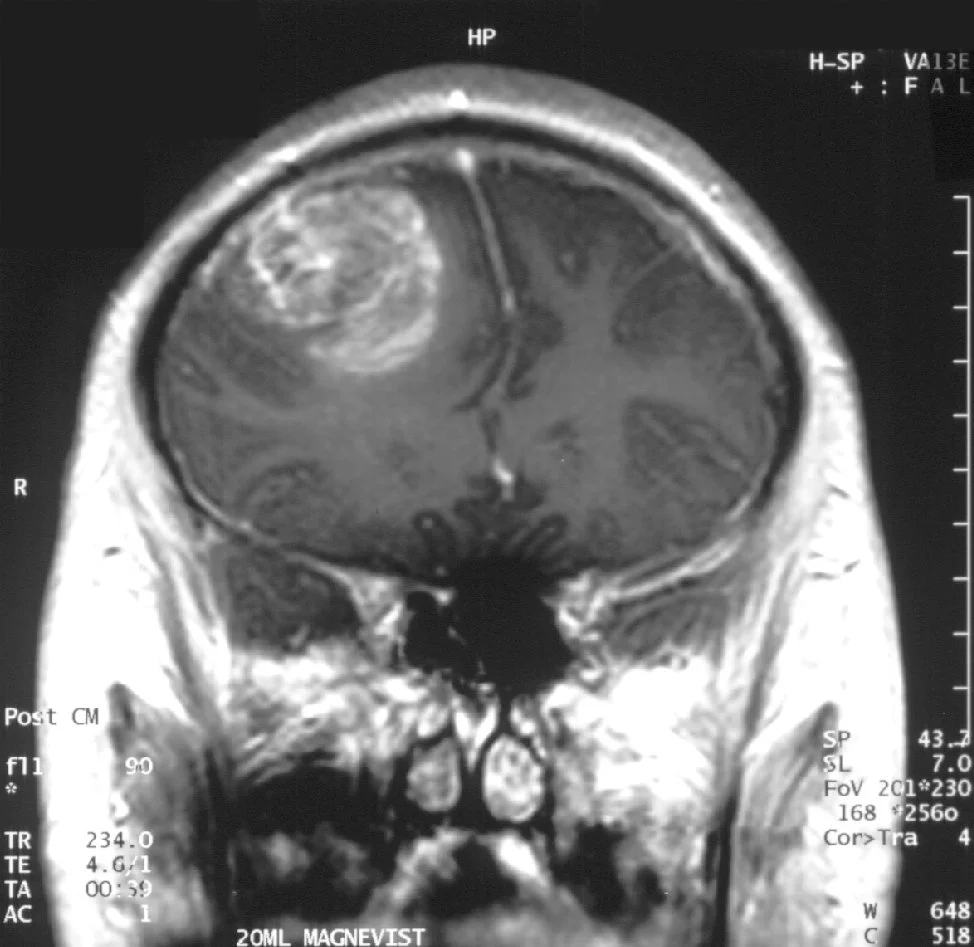

Com alguns ciclos de radioterapia sua imunidade piorou e o cansaço voltou. Contratou uma cozinheira para o preparo das refeições. Com a ajuda conseguiu manter-se na dieta. Esta estratégia, combinada com a radioterapia reduziu o glioblastoma no exame de imagem a um tamanho imperceptível. Após 40 meses de tratamento está dentro do peso ideal e sente-se menos cansada. Encontra-se bem fisicamente e segue mantendo os níveis de cetonas entre 1-2 mmol/L. Sua maior motivação para continuar é poder ver os netos crescendo.